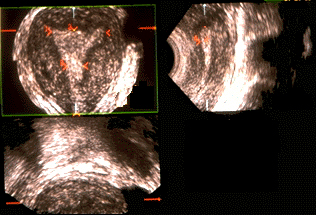

Utérus normal 3D. L'aspect de triangle cavitaire et ses éventuelles variantes, peut être observé. L'isthme et les parties interstitielles des trompes sont également bien visualisés. Sur la coupe frontale 3 D, on observe les variations de forme autour du triangle classique.

Large corne à droite.

Aspect convexe du fond cavitaire en bas à gauche.

L'étude en surface et en rotation permet une impression de coupe montée macroscopique.